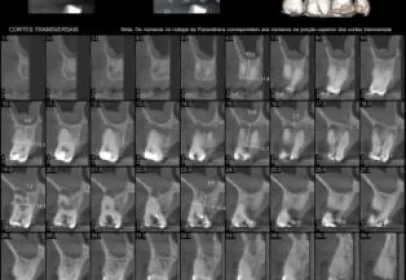

A Tomografia da Mandíbula é um exame de imagem que utiliza raios-X para criar imagens detalhadas e em alta resolução da região, incluindo a dentes,osso alveolar e base óssea . É frequentemente...